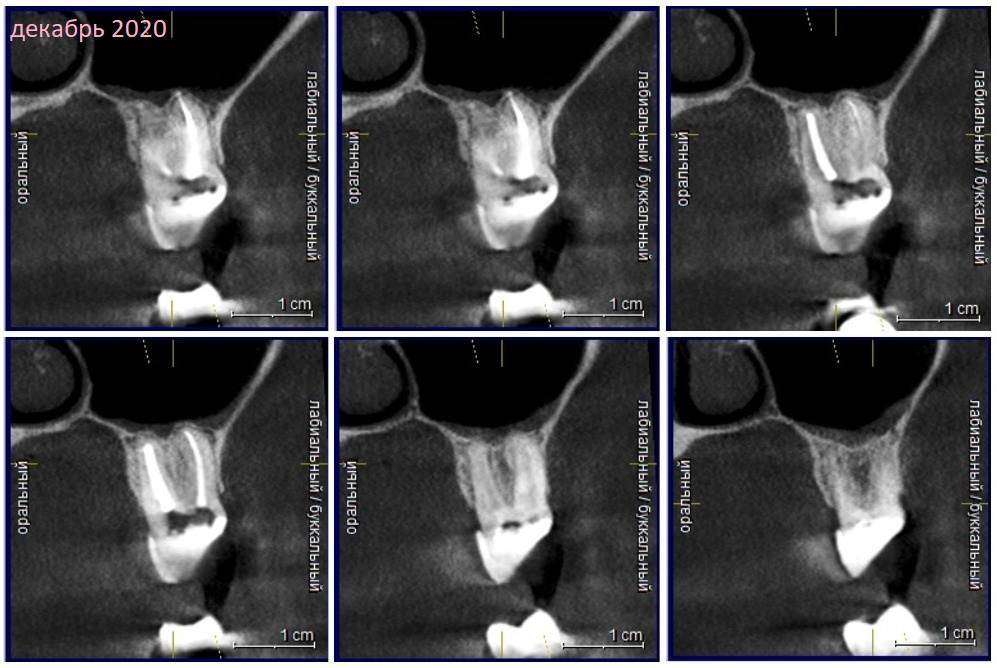

Зуб 17.

Июль 2020 - последнее перелечивание под микроскопом. Опять решили перелечивать только небный канал. Очень больно в процессе( Доп каналов нет, трещин нет. После этого болел очень сильно дней 5. Потом поменьше, и где-то через пару недель все стало так, как было раньше.

По словам всех врачей, смотревших КТ, осталась только одна возможная причина – соседний зуб. Зуб 16 с периодонтитом, который был давно уже в таком состоянии, под вкладкой, никогда не болел. До этого не было возможности им заниматься, т к удалялись и крутились обе 6ки с другой стороны.  17 удалять по причине разрушенности не предлагали, перестанет болеть - восстановить коронкой.. Ну и еще предлагали и 16 и 17 полечить депофорезиком)

Декабрь 2020

907972000_20202.thumb.jpg.0ab4a97f703d5a15c89a75c1d13b9517.jpg

1823267092_20201.jpg.b31d8b323ecf0bd7bf55a7dda4cba0d9.jpg

55913587_20203.thumb.jpg.ba8999d990adfd84e9540a38cd2c3825.jpg